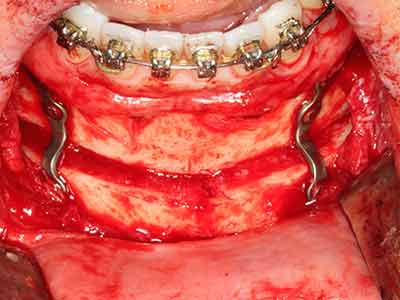

Aplicación: Partición ósea / Cortical Split

El tejido óseo no solo tiene un contenido puramente mineral, sino que también presenta una importante proporción de fibras de colágeno. Esto no solo garantiza una buena resistencia a la presión, sino también una cierta flexibilidad, que puede aprovecharse para la realización de aumentos. En la plastia de expansión clásica a efectos de una partición ósea, la cresta maxilar atrofiada se divide en su eje longitudinal y, tras alcanzar una profundidad de osteotomía suficiente, se extiende con cuidado (fig. 13-16), en un caso ideal sin desperiostizar de forma visible el maxilar (Brugnami, Caiazzo et al. 2014, Stricker, Fleiner et al. 2014). Los sistemas de tornillos y placas con distancia de expansión creciente han demostrado su eficacia para distanciar entre sí las dos tablas óseas por debajo del umbral de rotura. Por regla general, se requieren anchuras de hueso residual de al menos 3 a 4 mm (Chiapasco, Zaniboni et al. 2006) para garantizar una flexibilidad y una cobertura ósea suficientes de los implantes que van a incorporarse. En caso necesario, una osteotomía de descarga vertical unilateral o bilateral puede mejorar la flexibilidad. Como alternativa a la técnica clásica se ha descrito una combinación con otras técnicas de aumento, sobre todo en la parte bucal.

Con el uso de sierras piezoeléctricas la división se efectúa de forma especialmente cuidadosa y sin pérdidas importantes de las dimensiones, por lo que no se han encontrado diferencias significativas entre los implantes realizados en el maxilar dividido y en la cresta alveolar no deficitaria (Chiapasco, Zaniboni et al. 2006, Danza, Guidi et al. 2009). No obstante, precisamente en la partición profunda y limitada de forma local, es preciso asegurarse de que exista una adecuada irrigación por agua para evitar que se produzcan sobrecargas térmicas en las áreas de osteotomía apical.

Fig. 13: En este paciente de 52 años con una anchura del hueso residual del maxilar inferior de 4 mm, hay que asegurarse de que exista refrigeración por agua adecuada durante la partición del hueso.

Fig. 14: Incorporación de cuatro implantes RSX cónicos (Bego Implant Systems, Bremen).